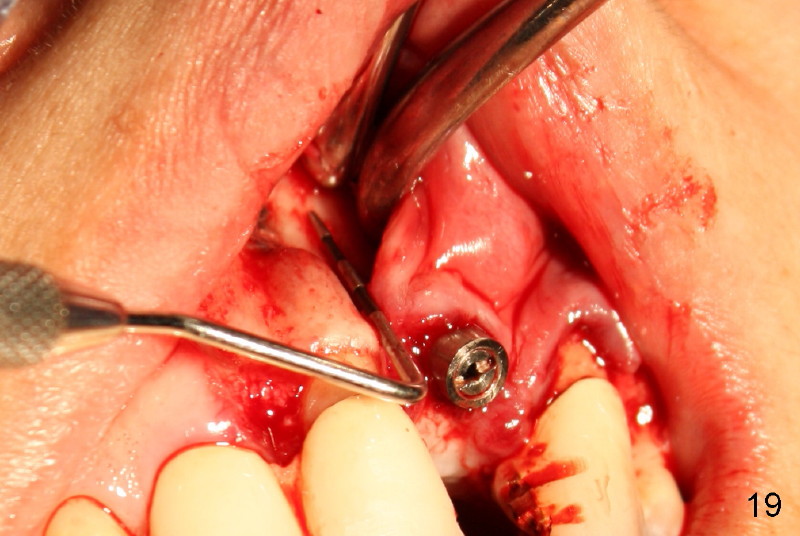

Segmental Osteotomy for Misplaced Implant

This corrective surgery was performed by Dr. Bernee Dunson.

Xin Wei, DDS, PhD, MS 1st edition 12/21/2011, last revision 12/23/2011